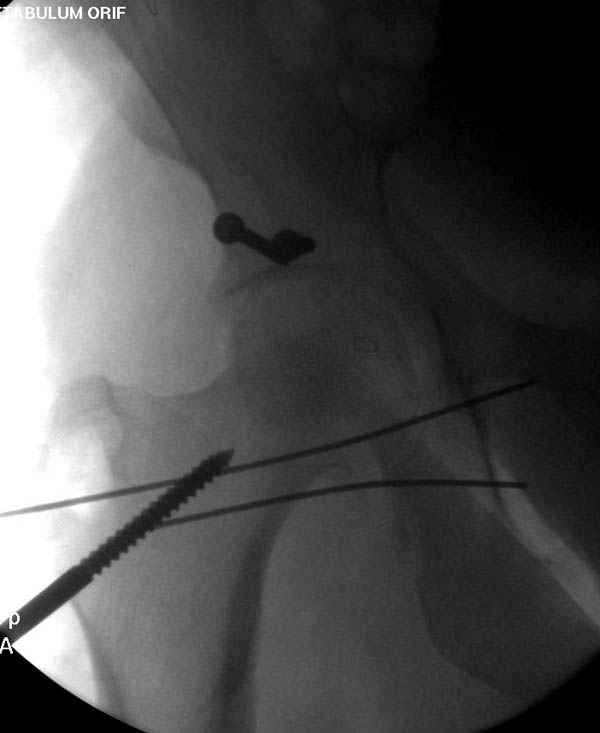

По снимку создается впечатление о высоком поперечном переломе, задней колонны, стенки; почему не пользовались *magic screw*?

Не хотелось отклонятся от основной темы, поэтому здесь краткие ответы..

Латеральное положение облегчает проведение тракции через вертел, за 5 мм стержень за вертел (грузом через тракционное приспособление), на обычном рентгенопрозрачном операционном столе, а для положения на животе, наверное, Judet Table более приемлем, потому что там имеется латеральное тракционное устроиство.

Там множество обычных 2.7 мм шурупов, потом идет фиксация основными пластинами.

Снимки здесь....